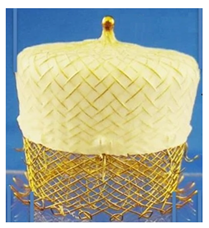

(Photo courtesy LifeTech Scientific) | LAmbre LifeTech Scientific | Double-disc design with umbrella-shaped anchoring disc and cover disc; eight distal hooks and eight U-shaped ends; multiple sizes for LAA up to 40 mm, smaller delivery sheath (10.4–12.3 Fr). | Cases of device misalignment leading to significant PDL and minor PDL not uncommon. |